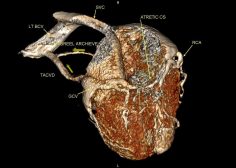

Atretic coronary venous sinus ostium ( CS) , Total Anomalous Coronary Venous Drainage to LT BCV (TACVD).

The middle & great cardiac veins (MCV & GCV) drain into a left sided vertical vein ( same course of persistent LSVC) to left BCV & also a vein draining the anterior wall of the RV ending into the left vertical vein . U must notify the surgeon this item so as not to ligate this thought persistent LSVC / vertical vein to any reason as in partial cavo-pulmonary connection (Glenn shunt) otherwise catastrophic sequale will happen.

so in any congenital CT study make sure the CS ostium is patent & not atretic.